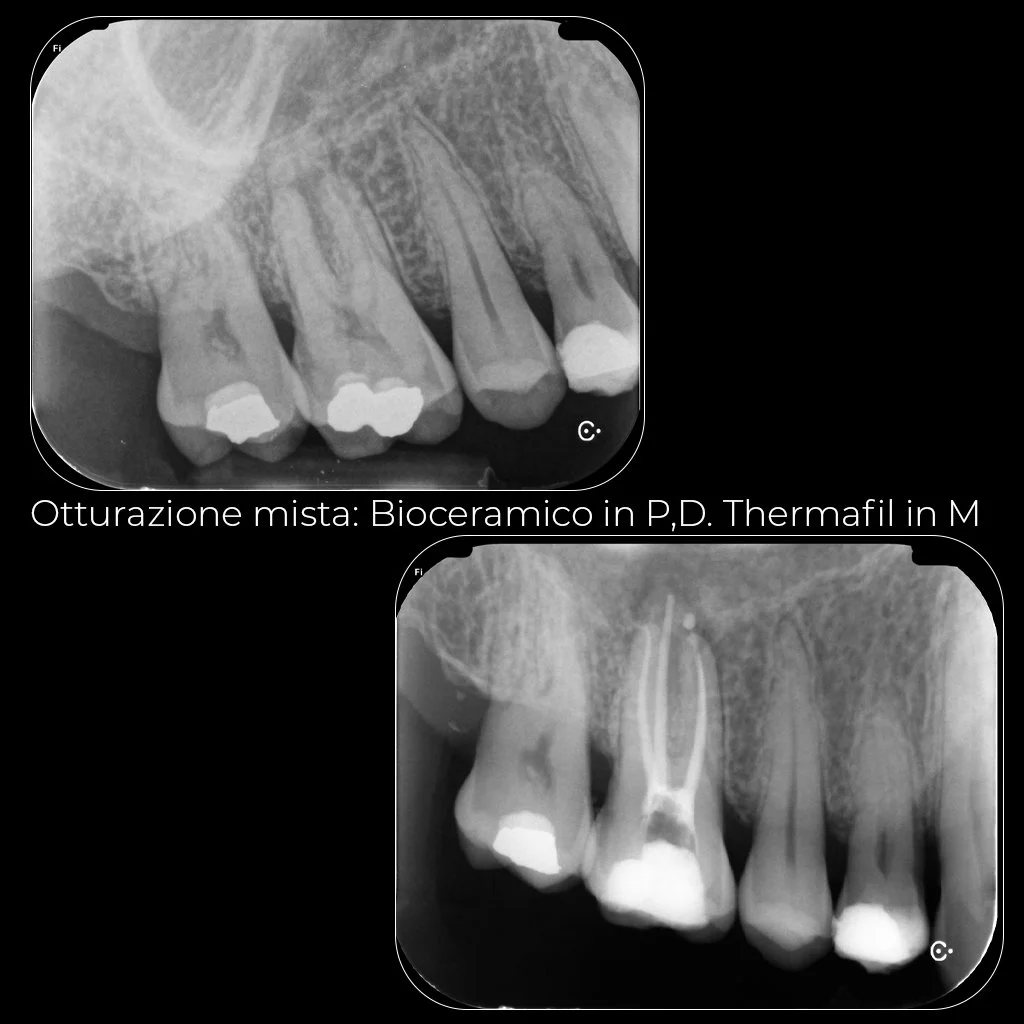

Endodonzia

Casi Complessi